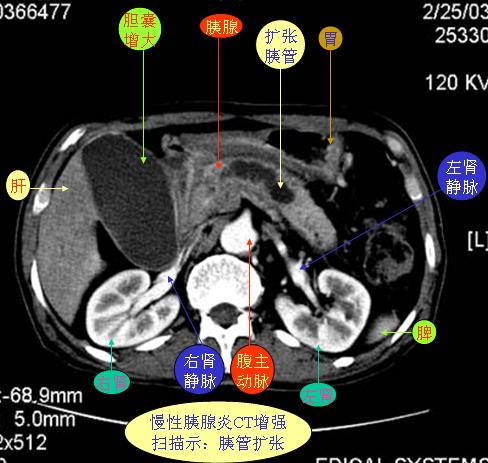

腹部ct解剖与基本病变